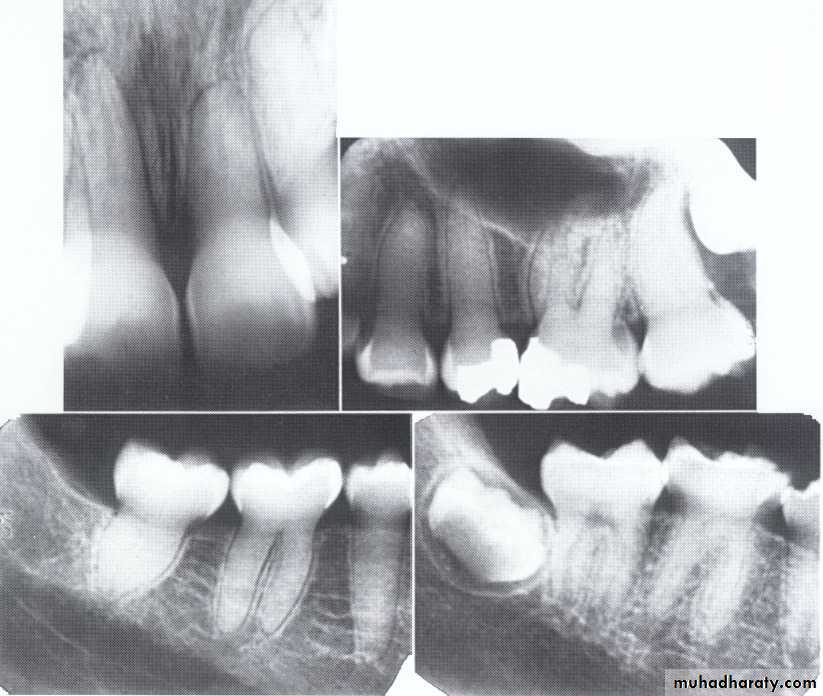

Dentin dysplasia, type I. panoramic & periapical films of the same case show the short and poorly developed roots, obliterated pulp chambers and root canals, and periapical inflammatory lesions.